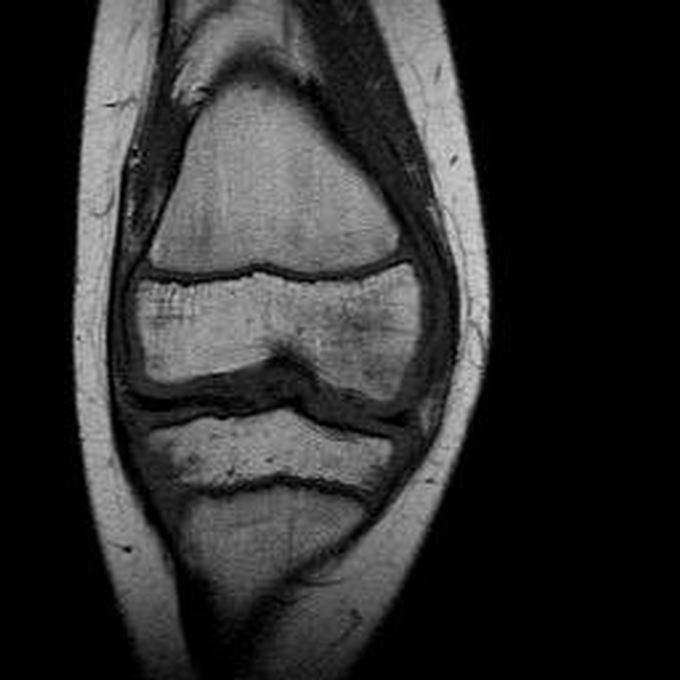

Haemophiliearthropathie bei Haemophilie A.

ARC123 Haemophiliearthropathie bei Haemophilie A.